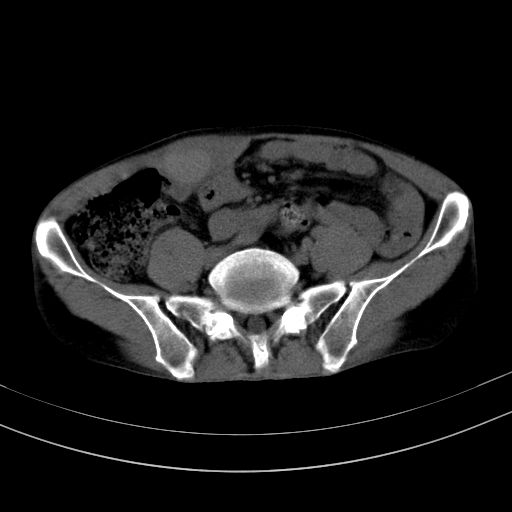

以下是引用37度在2010-1-9 14:37:00的发言:[br]1.双肾囊肿,左肾积水结石,.胆总管轻度扩张;[br]2.病灶在腹膜外,考虑纤维瘤。

以下是引用dyqct在2010-1-9 17:56:00的发言:[br]考虑:1.双肾囊肿,左肾积水结石、旋转不良。[br] 2.右侧腹直肌血肿或纤维瘤。[br]肠道准备不好。做个增强。